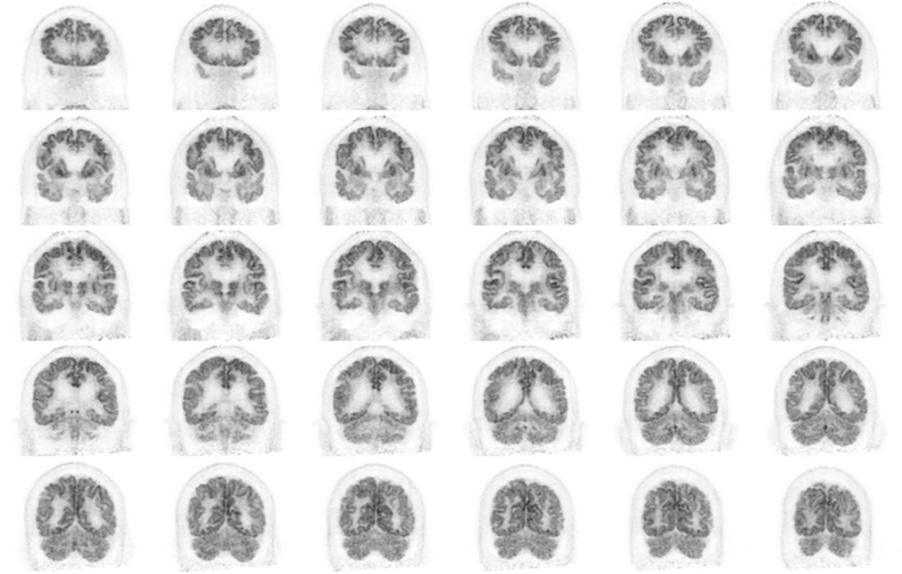

Head / Case2 : FDG

Coronal

Courtesy : Kindai University Hospital

- Imaging protocol

- Injected dose: 3.29 MBq/kg, 18F-FDG

- Uptake time: 38 minutes

- Scan time: 30 minutes